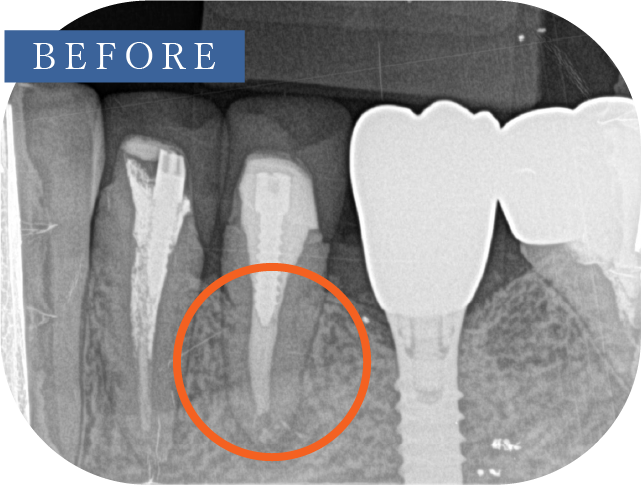

(根尖切除術・意図的再植術)